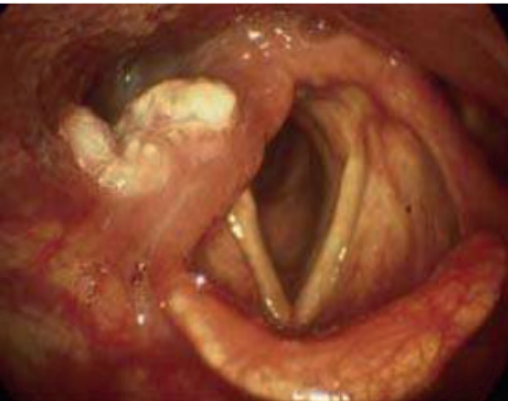

Processos de proteção da via respiratória. Fonte: Acervo de ilustrações do Grupo MedCof.

Endoscopia mostrando pregas vocais. Fonte: Acervo de aulas do Grupo MedCof.

As Pregas Vocais (PPVV) possuem múltiplas camadas, incluindo o Espaço de Reinke (camada superficial da lâmina própria). A musculatura intrínseca modula a posição e tensão das PPVV: